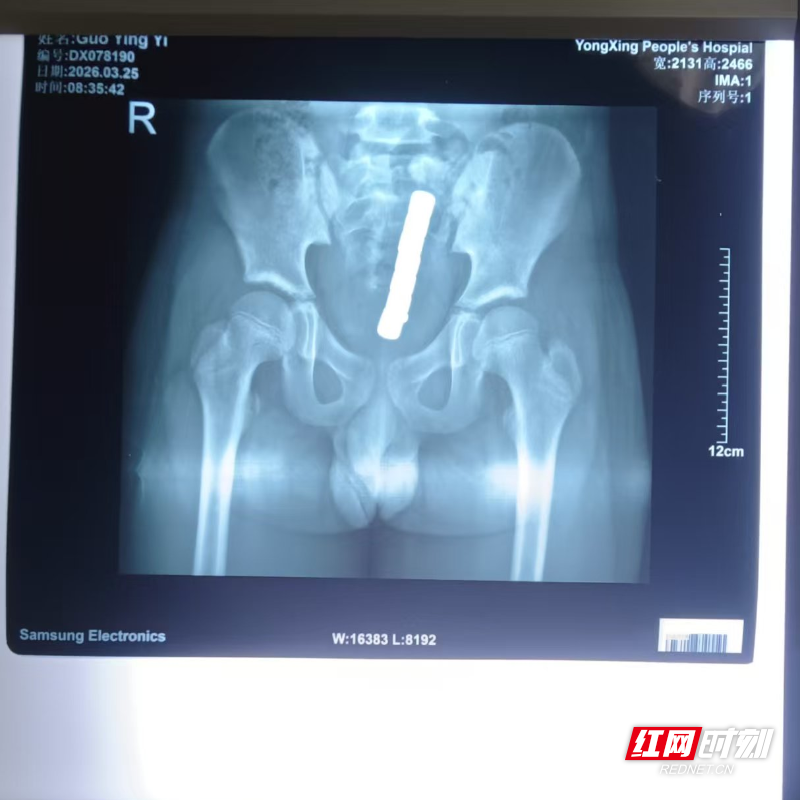

起初,家长并未察觉异常,直到小颖出现持续腹痛、腹胀等不适,使用开塞露通便后仅排出5颗磁力珠,剩余3颗滞留体内。家人紧急送医,经检查确诊为直肠穿孔,情况十分危急。

该院小儿普外科主任王国彦介绍,多颗磁力珠进入直肠后,会因磁力相互吸附,持续夹紧肠壁,造成局部组织缺血、坏死,最终引发肠道穿孔。手术中,医生发现小颖肠道存在多处穿孔,随即为其实施直肠修补术+乙状结肠造口术+内镜下直肠内异物去除术。经过医护团队精心护理,小颖腹腔感染得到有效控制,肠道功能逐步恢复,但仍需在三个月后接受造口回纳手术。

医生提醒,儿童误吞或误塞磁力珠,切勿自行处理。无论是否出现不适症状,一旦发现需立即送医,通过X光、CT等检查明确异物位置与数量,评估肠道损伤程度。未造成严重损伤时,可通过内镜微创取出;若已出现穿孔、梗阻,则必须紧急手术干预。